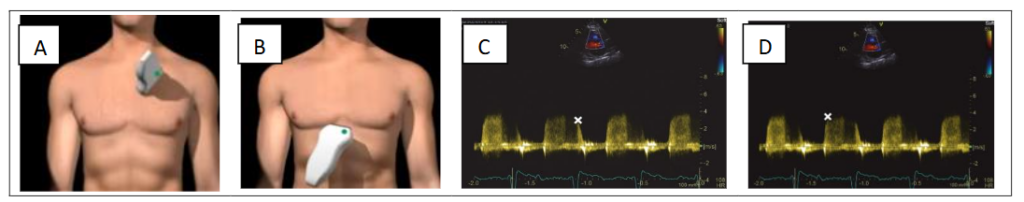

STEP 3 – DE ESTIMATION OF PULMONARY ACCELERATION TIME (AcT) AND PULMONARY ARTERY DIMENSION

In PH, early pulmonary ejection may be increased, resulting in a short acceleration time. A complementary method for pressure assessment utilizes the AcT of the pulsed wave (PW) Doppler flow velocity in the right ventricular outflow tract (RVOT). This measure is simple, reproducible and correlates inversely with the mPAP. PW Doppler measurement after positioning the sample volume just below the pulmonary cusp on the right ventricle side in the RVOT outflow tract.

Measure at the end of expiration from the onset of flow to peak flow velocity. As pulmonary artery pressure (PAP) increases, the acceleration time of right ventricular ejection into pulmonary artery decreases.

Use the average of five beats for atrial fibrillation. Heart rates (HR) outside the normal range (<70 or >100 bpm) may affect accuracy and a correction for HR may be used (RVOT AT × 75/HR). Correlations between sPAP and time to maximal pulmonary blood velocity (AcT measured by PW Doppler echocardiography) are strong. In addition, AcT may be a better marker of pulmonary artery impedance or right ventricular afterload than pressure. That is, in two patients with the same mPAP, the patient with a high AcT (i.e. >100 ms) will have a relatively normal pulmonary vascular resistance (PVR), whereas a patient with an AcT of less than 100 ms is more likely to have an elevated PVR and right ventricular afterload.

On PW or CW Doppler examination of the RVOT, a notch can be seen in the centre of the systolic cavity. This notch is thought to be caused by the reflection of the pressure wave reflection at the increased PVR, which temporarily decreases the forward velocity. The presence of a pulmonary systolic notch is considered a marker for an elevated PAP; a pulmonary notch in mid-systole indicates increased PVR and poor vascular compliance, which corresponds to precapillary PH rather than PH due to left heart disease; pulmonary AcT of less than 90 ms predicts a PVR of more than 3 Wood Units and PH (figure 3).

Figure 3. Parasternal (A) and subcostal (B) views. DE estimation of pulmonary artery dimension and pulmonary acceleration time (AcT). PA diameter >25 mm (arrow) (C). Representative Doppler tracings without evidence of Doppler notching (D). Examples in the mid-systolic notch (arrows), characterized by a distinct notch or nadir in its mid portion, dividing the flow profile into 2 distinct peaks (E); doppler tracings with a late systolic notch (F).

ADDITIONAL DE MEASURES CAN CONTRIBUTE TO CLINICAL DEFINITION AND THERAPEUTIC DECISION, AND INCLUDE ESTIMATION OF DIASTOLIC PAP (dPAP) AND mPAP.

Mild pulmonary regurgitation (PR) has been found in 40–78% of patients with morphologically normal pulmonary valves and no other signs of structural heart disease. Pathological regurgitation is infrequent; significant PR occurs in approximately 30% of patients with PH.

With CW and PW Doppler echocardiography, it is possible to estimate the diastolic pressure in the pulmonary artery (dPAP) in PR, especially when significant structural abnormalities of the right heart are present. Colour Doppler flow mapping is the most commonly used method to identify PR. A diastolic jet in the right ventricular outflow tract (RVOT) that starts at the coaptation line of the heart valves and is directed towards the right ventricle is diagnostic for PR.

PR velocities are measured from the parasternal short axis and in the subcostal views using PW in RVOT. However, there is no clinically recognized method for quantifying pulmonary regurgitation using CW Doppler; the density of the CW signal provides a qualitative measure of regurgitation. Although rapid deceleration is associated with more severe regurgitation, it is influenced by several factors, including RV diastolic properties and filling pressures.

dPAP and mPAP can be estimated: PR (pulmonary jet profile using the modified Bernoulli equation as for TRV) and RAP; dPAP = 4× (PR end velocity of PR jet velocity)² + RAP (normal value < 15 mmHg) and mPAP = 4× (PR in velocity of PR jet)² + RAP where PR end is the end PR velocity and PR in is the initial PR velocity. An early PR velocity >2.2 m/s is considered a marker for increased mPAP. Although this measurement is subject to high inter-observer variability, a jet width that is >65% of the RVOT width measured in the same frame is indicative of severe PR (figure 5).

Figure 5. Parasternal short-axis (A) and subcostal (B) views. Measurement of pulmonary regurgitant jet at in-(C) and end-(D) diastole (marked X).